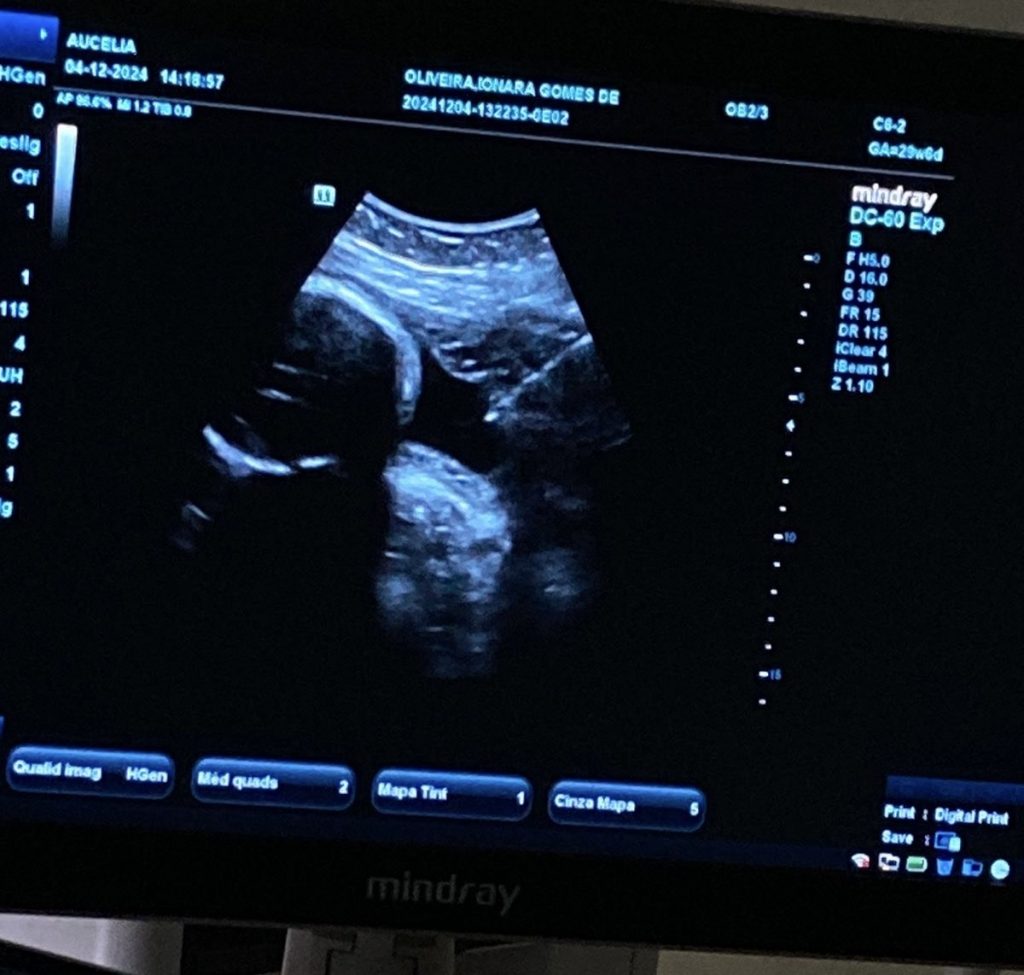

O Instituto Cândida Vargas (ICV), unidade referência em saúde materno-infantil vinculada à Prefeitura de João Pessoa, realizou nesta semana a primeira amniocentese em sua sala de ultrassom. O procedimento foi realizado com o objetivo de diagnosticar, de forma intrauterina, uma possível infecção fetal por toxoplasmose e direcionar o tratamento conforme as normativas do Ministério da Saúde.

A paciente apresentava sorologia positiva para toxoplasmose, mas o diagnóstico de infecção fetal só poderia ser confirmado por meio da análise do PCR do líquido amniótico, coletado durante a amniocentese. Esse exame é essencial para garantir o tratamento adequado e prevenir complicações para o bebê. O procedimento foi realizado pela equipe de Medicina Fetal, liderada pela Dra. Daniela Aires e pela Dra. Patrícia Azevedo.